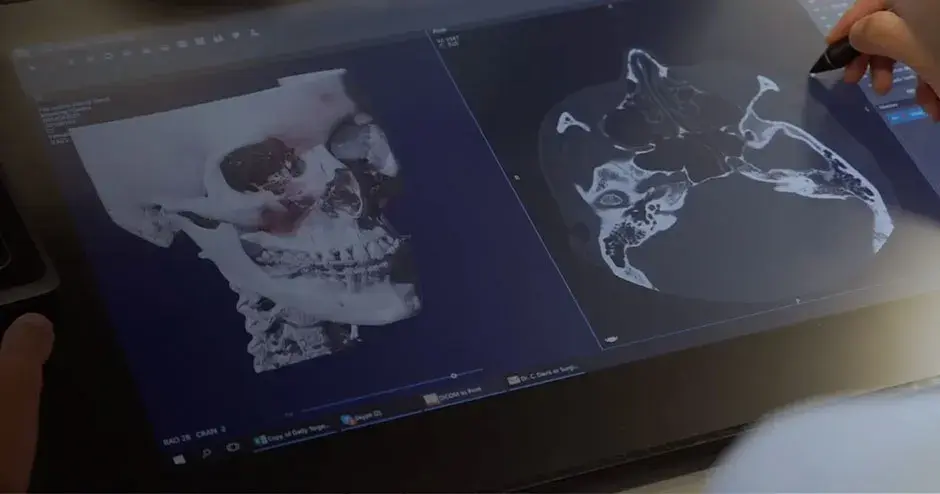

3D Systems' VSP® surgical planning solutions for craniomaxillofacial (CMF) applications received FDA clearance as a service-based approach to personalized surgery over 10 years ago.

3D Systems and Stryker Corporation have partnered to provide surgeons with best-in-class products and services for craniomaxillofacial surgeries. As a leader in personalized healthcare solutions, 3D Systems has planned and delivered devices for more than 140,000 patient-specific cases. The Stryker Craniomaxillofacial business specializes in providing patient-specific options and innovative solutions that help drive efficiencies in surgical suites. The combination of Stryker’s specialized team and advanced implants with 3D Systems' cutting-edge 3D printing technologies and expert consulting services positions both companies to provide a superior level of service to healthcare professionals who use these revolutionary solutions.